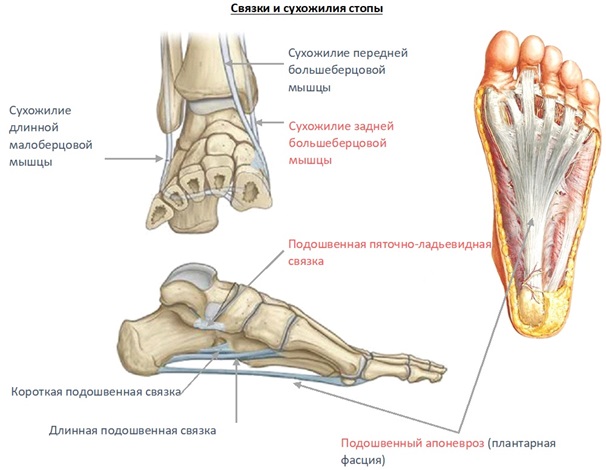

Анатомия подошвенной мышцы голени: подробное рассмотрение